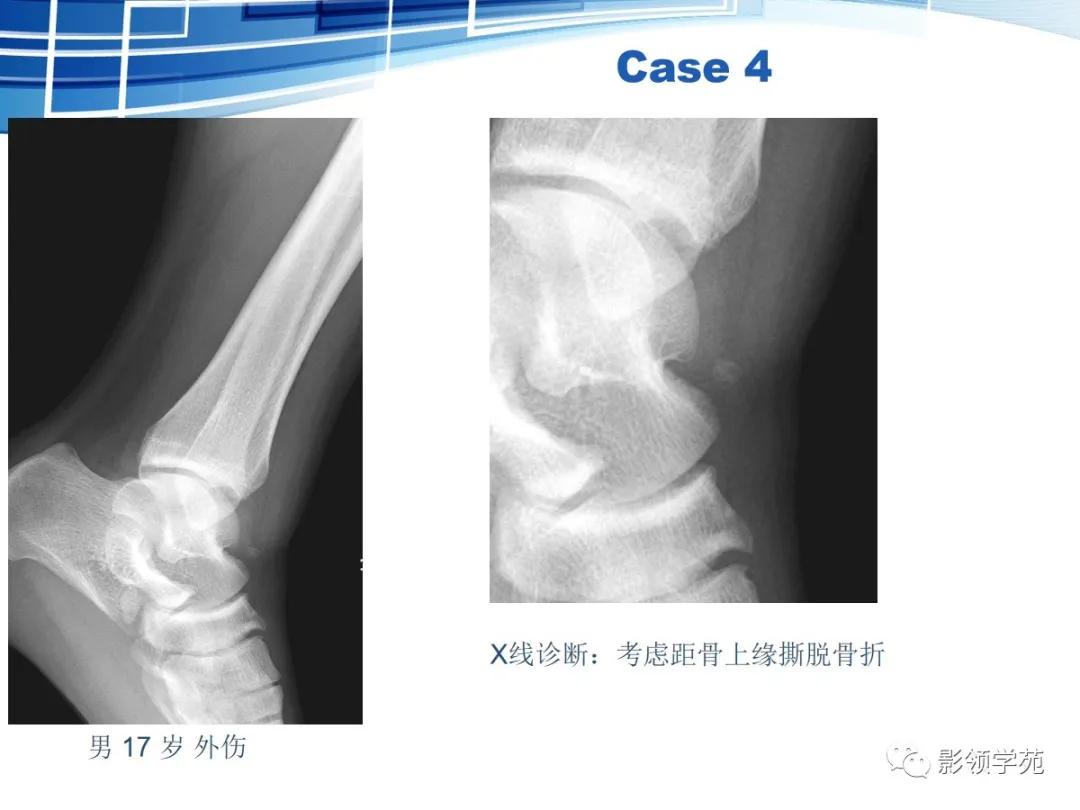

撕脱性骨折的影像学特征

具有典型的好发部位,如肱二头肌肌腱附着处撕脱引起的肱骨大结节撕脱骨折。

具有骨折的直接、间接征象,例如撕脱后的游离骨及所对应的受损骨,其骨皮质不连续或缺损,且其边缘锐利、清晰(CT更能清楚显示);MRI可示局部软组织肿胀、积液或积血等改变;最有利的证据是伤后一段时间,上述征象发生了如边缘骨质吸收、有骨硬化、骨痂生长、局部软组织肿胀消退等动态改变。

撕脱骨块脱离后位移方向与其损伤机制密切相关。

撕脱性骨折多病情急、病程比较短。

虽然撕脱性骨折与永存骨骺、籽骨和副骨在影像学上均有游离的小骨块影的表现,但前者具有骨折的影像学一般特征,而后三者不具有。

鉴别重点:独立的骨结构(游离骨)若与相对骨的缺损缘相吻合,是撕脱,如有外伤,更支持。